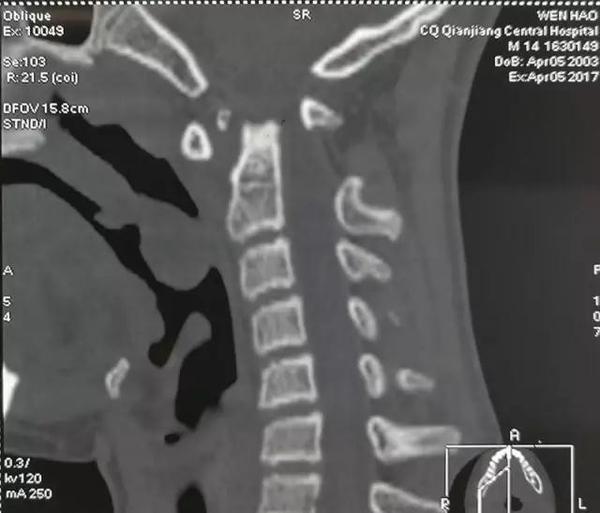

术前影像资料

1、脊髓损伤

2、颅颈畸形:寰枢椎半脱位,齿状突不连续